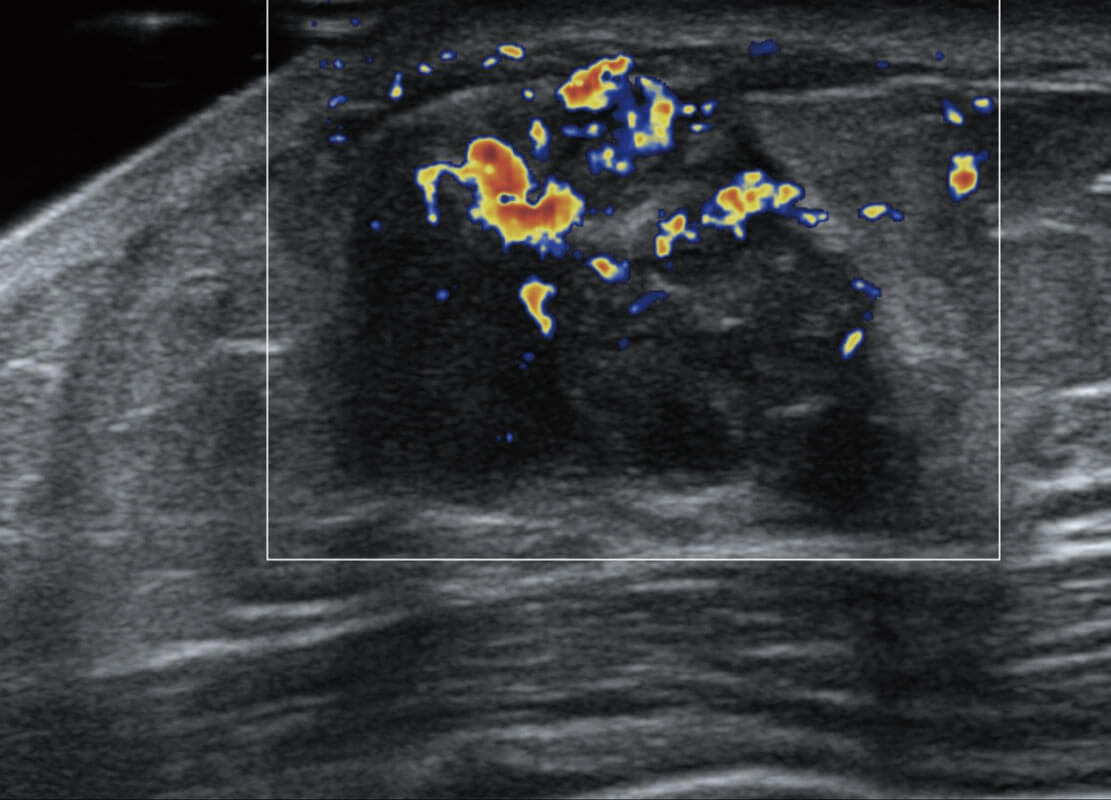

乳腺导管癌

乳腺癌显微血流